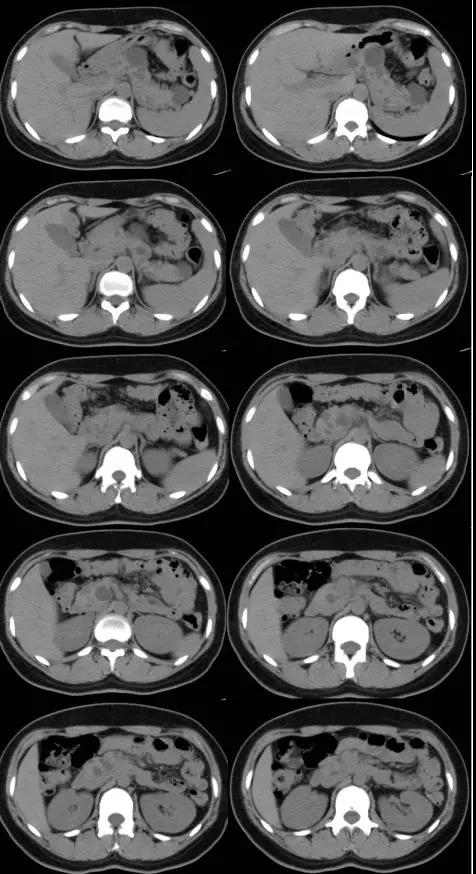

影像诊断为双侧小脑半球占位性病变,考虑血管母细胞瘤或毛细胞型星形细胞瘤。患者次日又做了全腹部CT,CT示胰腺多发囊肿,余未见明显异常(图2)

胰腺病变:35%~70%的患者并发胰腺病变,约12%的患者以胰腺病变为唯一的腹腔病变,包括单纯性囊肿、浆液性囊腺瘤、胰腺内分泌肿 瘤、转移癌等,前两者最多见。胰腺囊肿早期无症状,腹部CT见胰腺多发圆形或类圆形低密度影,边界清晰,囊壁可见钙化。胰腺神经内分泌肿瘤中无功能性肿瘤较功能性 肿瘤多见且血供更丰富,CT呈等密度影,边界欠清,增强扫描可见明显均匀强化。